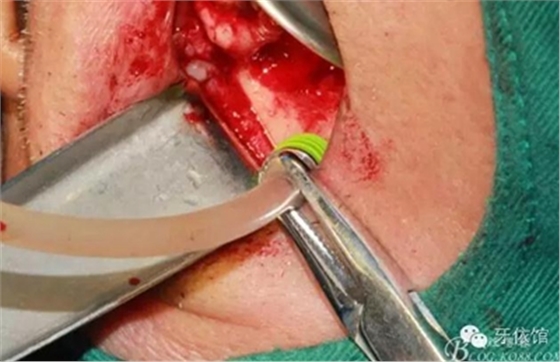

分離洞邊緣膜

CAS水壓剝離頰側(cè)竇膜(安全省事)

開窗永磁鉆

取下骨片可以看到,膜已經(jīng)剝離

擴(kuò)大剝離面積